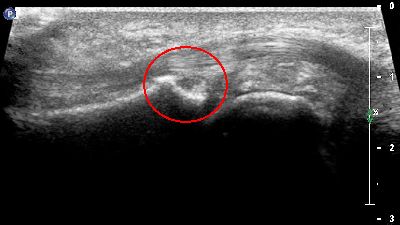

Cisti cisti 1